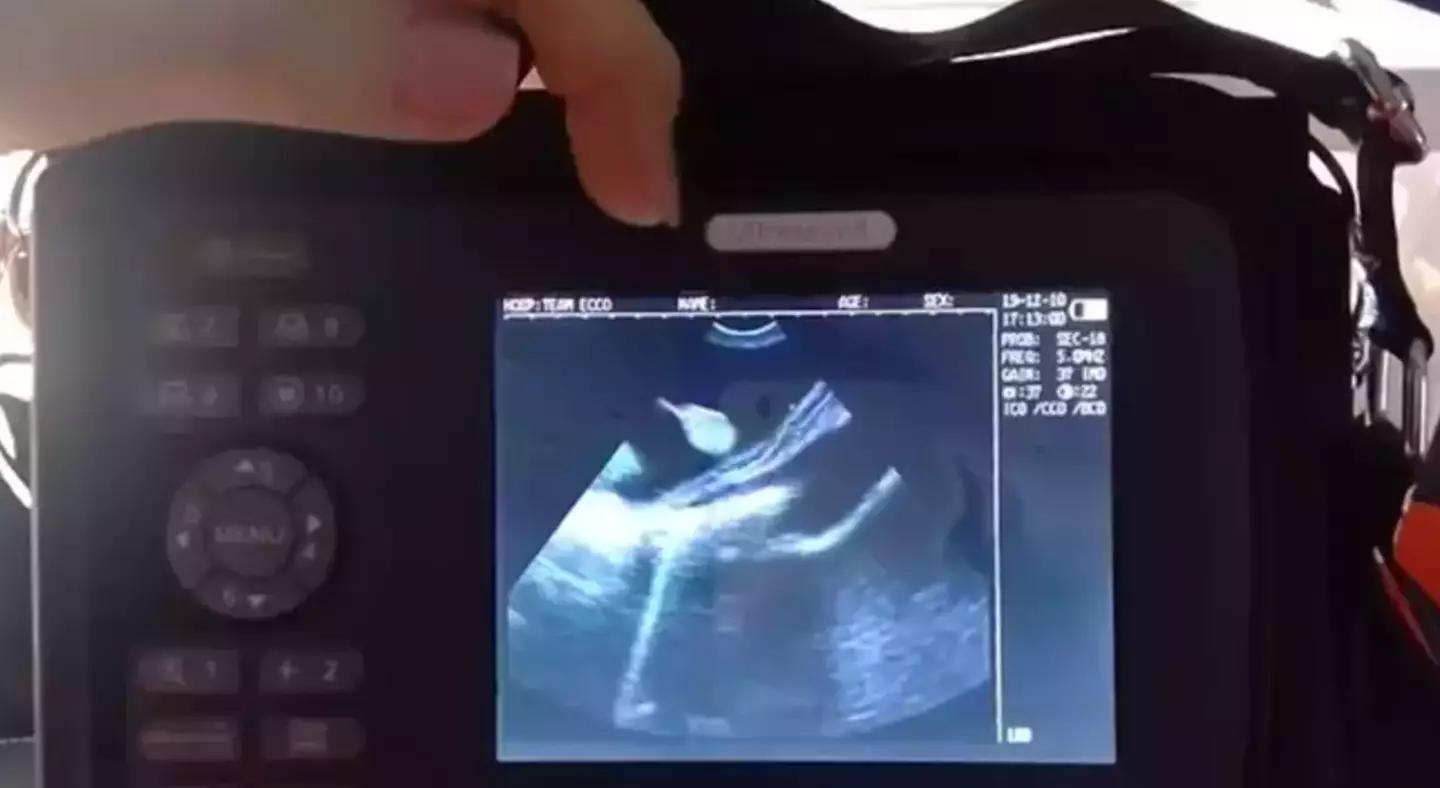

The experts carried out an ultrasound, but shockingly found out that Charlotte was actually now pregnant with four pups. Now, in February 2024, she is not far off her delivery date.